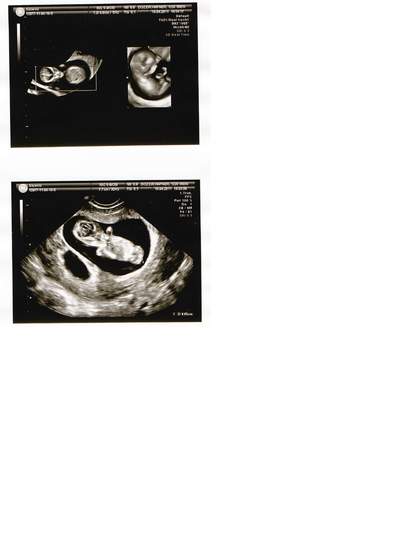

Jestem juz po wizytce i dziekuje za Wasze kciuki-> przydaly sie. Maluszki kompletnie zdrowe, oboje identycznej wielkosci, 4,85 cm, przeziernosc karkowa idealna. I co najwazniejsze, wedle mego lekarza, ktory zrobil obraz 3d na 80-90% bedzie chlopczyk i dziewczynka. Jestem przeszczesliwa.

11t3d_a.jpg11t3d.jpg